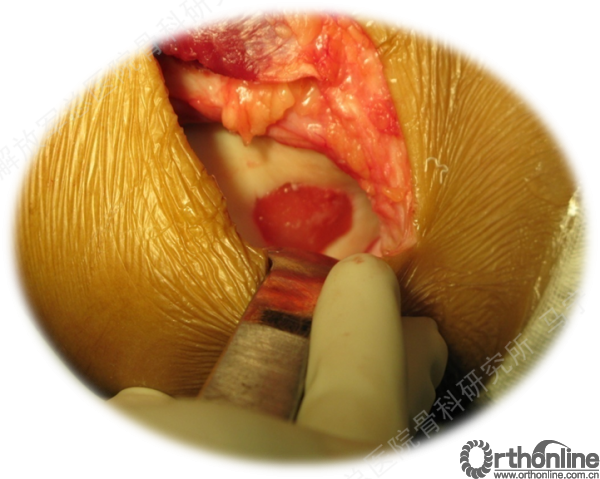

切开后可以看见很明显的软骨破坏。

对糜烂的软骨进行清创,按照损伤的面积裁剪软骨补片进行修补。